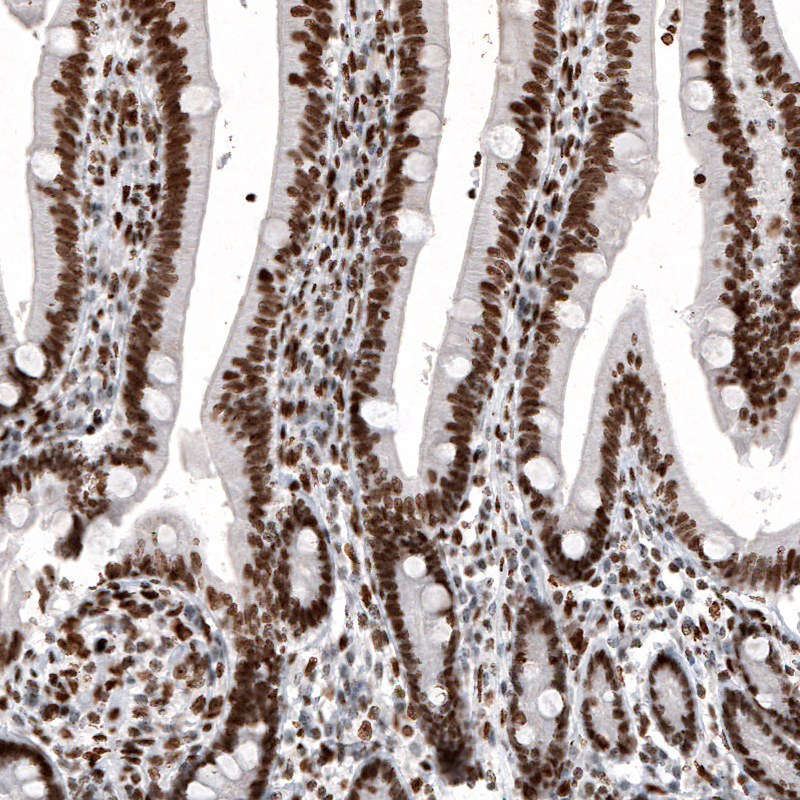

Immunohistochemical staining of human duodenum shows strong nuclear immunoreactivity in glandular cells and in lamina propria cells.